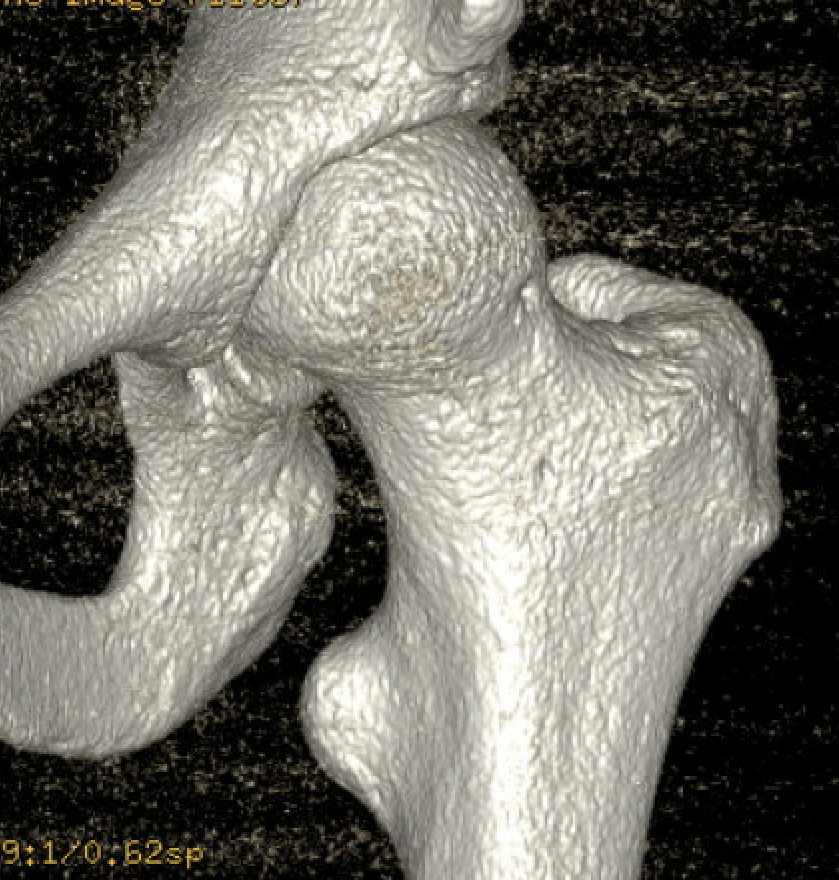

CT

- enlarged lesser trochanters

- increased proximal femoral anteversion

- coxa valga

- proximal femoral fractures

- osteochondromas